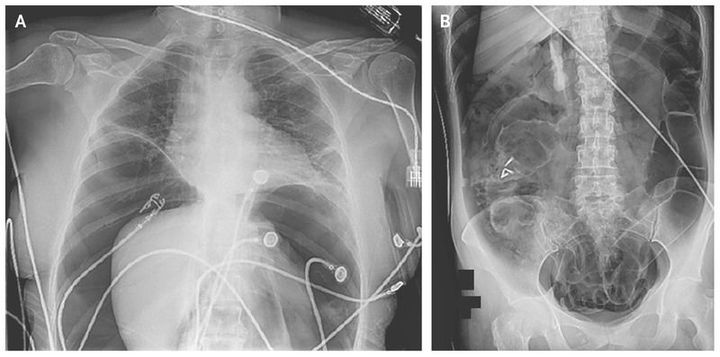

A 65-year-old woman who had undergone colonoscopy with removal of multiple polyps had become unresponsive at the end of the procedure and was transferred to the emergency department for evaluation. She regained consciousness but remained in distress with diaphoresis. On physical examination, the heart rate was 130 beats per minute, and the skin of the abdominal and pelvic areas and lower limbs was mottled. The abdomen was massively distended, tympanitic, and diffusely tender to palpation with evidence of guarding. Chest and abdominal radiographs (Panels A and B) revealed a large amount of free air under the diaphragm with centralization of the intraabdominal contents that was consistent with a massive tension pneumoperitoneum. The patient was taken to the operating room, where she underwent a decompressive laparotomy (Video) and a wedge partial colectomy to correct an iatrogenic perforation of the ascending colon. The patient had an uneventful recovery and was discharged home on the third postoperative day.